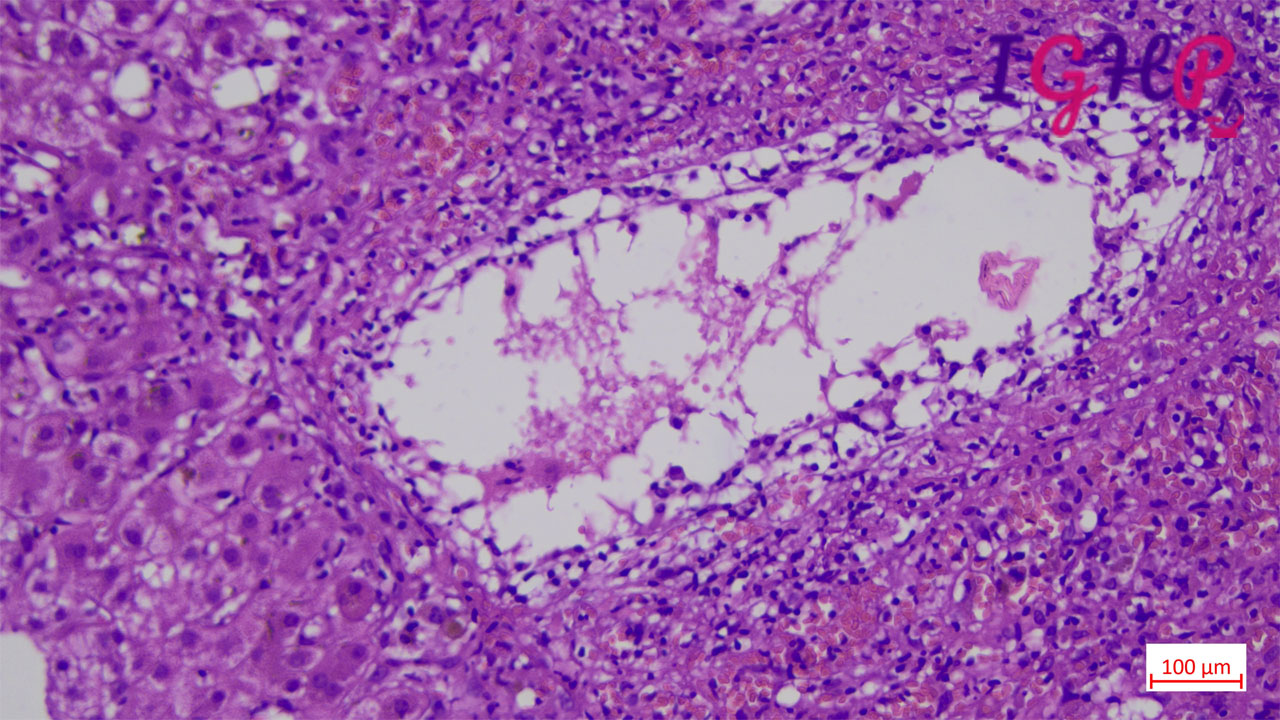

Microscopic Images-

Microscopic examination showed an areas of perivenular hepatocyte loss with prominent central perivenulitis.